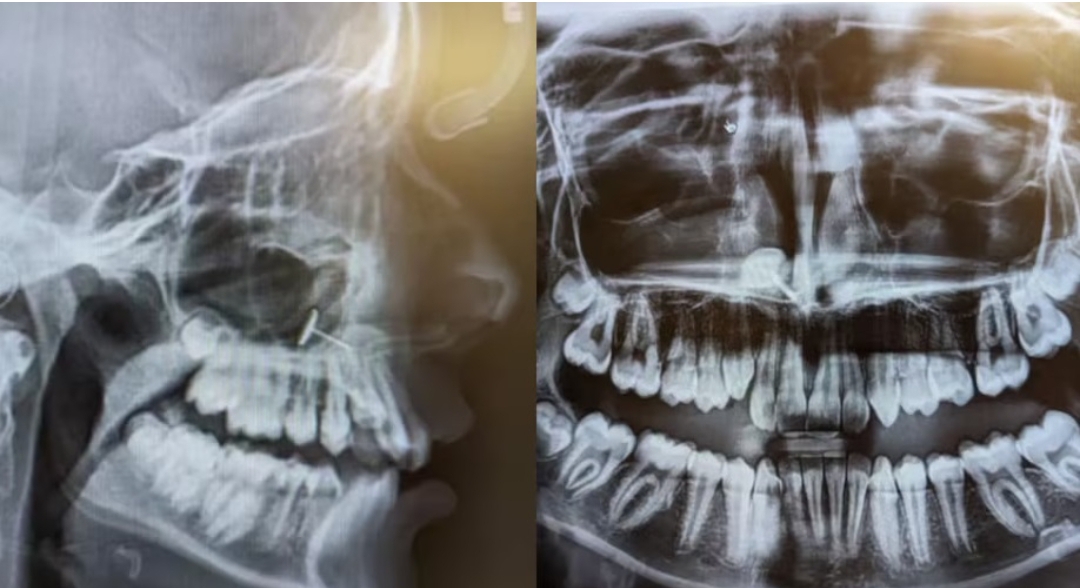

अमेरिका के वॉशिंगटन स्टेट में एक 13 साल की बच्ची का साधारण डेंटल चेकअप मेडिकल मिस्ट्री बन गया। बेटी ब्रेसेज के लिए ऑर्थोडॉन्टिस्ट के पास गई थी लेकिन एक्स-रे ने चौंकाने वाला राज खोल दिया—उसकी साइनस में धातु का एक छोटा-सा टुकड़ा फंसा हुआ था।

ओफीलिया (बदला हुआ नाम) अपनी बेटी को ब्रेसेज लगवाने के लिए डॉक्टर के पास ले गई थीं। एक्स-रे स्क्रीन पर जब तस्वीर सामने आई तो डॉक्टर और परिवार दोनों हैरान रह गए। ओफीलिया ने बताया—”साइनस में धातु का टुकड़ा साफ दिख रहा था, हम समझ ही नहीं पा रहे थे कि ये वहां कैसे पहुंचा।”

दरअसल, घटना छह महीने पुरानी थी। बेटी को ADHD (Attention Deficit Hyperactivity Disorder) है जिसकी वजह से वह अपने आवेगों को नियंत्रित नहीं कर पाती थी। मां के मना करने के बावजूद उसने खुद ही इयररिंग से नाक छेदने की कोशिश की। इस दौरान धातु का छोटा हिस्सा नाक से होकर साइनस में चला गया। डर की वजह से बच्ची ने यह बात अपनी मां से छिपा ली।

सौभाग्य से, यह मामला बिना किसी दर्दनाक परिणाम के खत्म हुआ। एक ENT विशेषज्ञ ने लंबी चिमटी की मदद से धातु के टुकड़े को निकाल दिया। बच्ची को बिल्कुल दर्द नहीं हुआ।